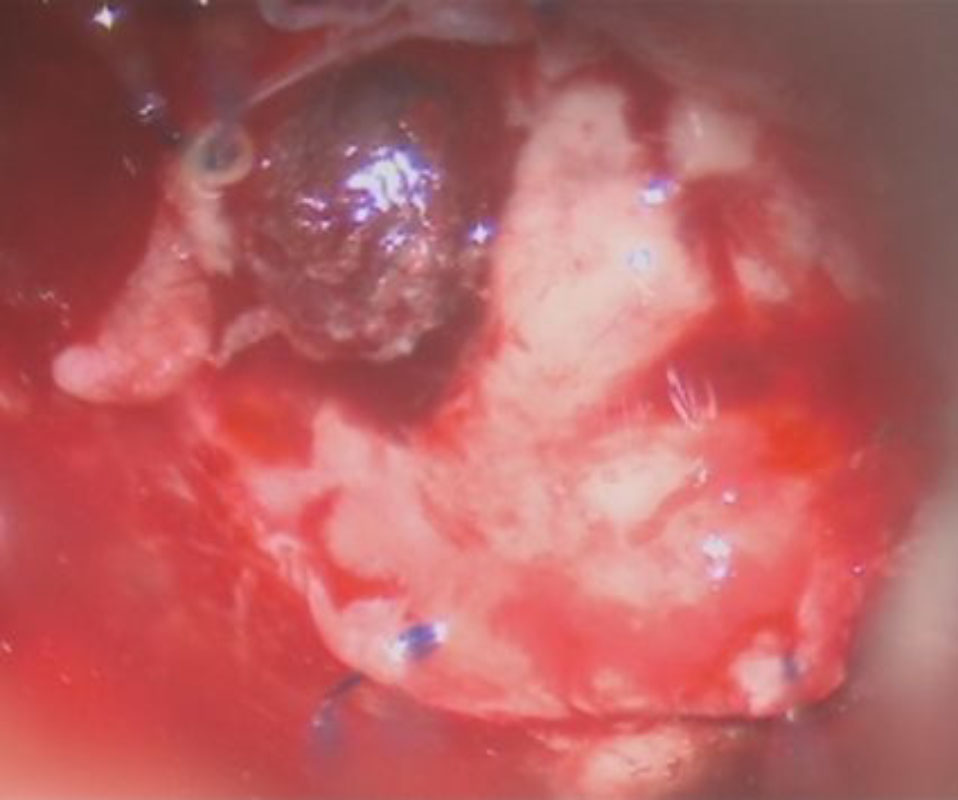

摘出 中